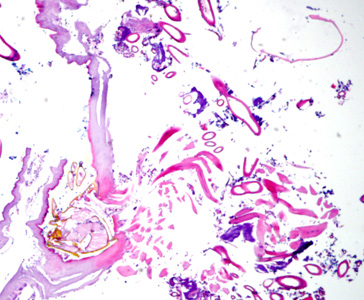

Case #275 – May, 2010

A 70-year-old female, who had recently returned from a trip to Madagascar, went to the hospital for a painful sensation on the underside of her left foot while walking. Examination of the area between the hallux and index toes revealed an ulcerative lesion. A biopsy was performed and sent to the Pathology Department for work-up. The specimen was sectioned, stained with hematoxylin and eosin (H&E) and examined by the attending pathologist. Figures A and B show what was observed at 40x magnification. Figures C and D show the same fields at 200x magnification, respectively. What is your diagnosis? Based on what criteria?

Figure A